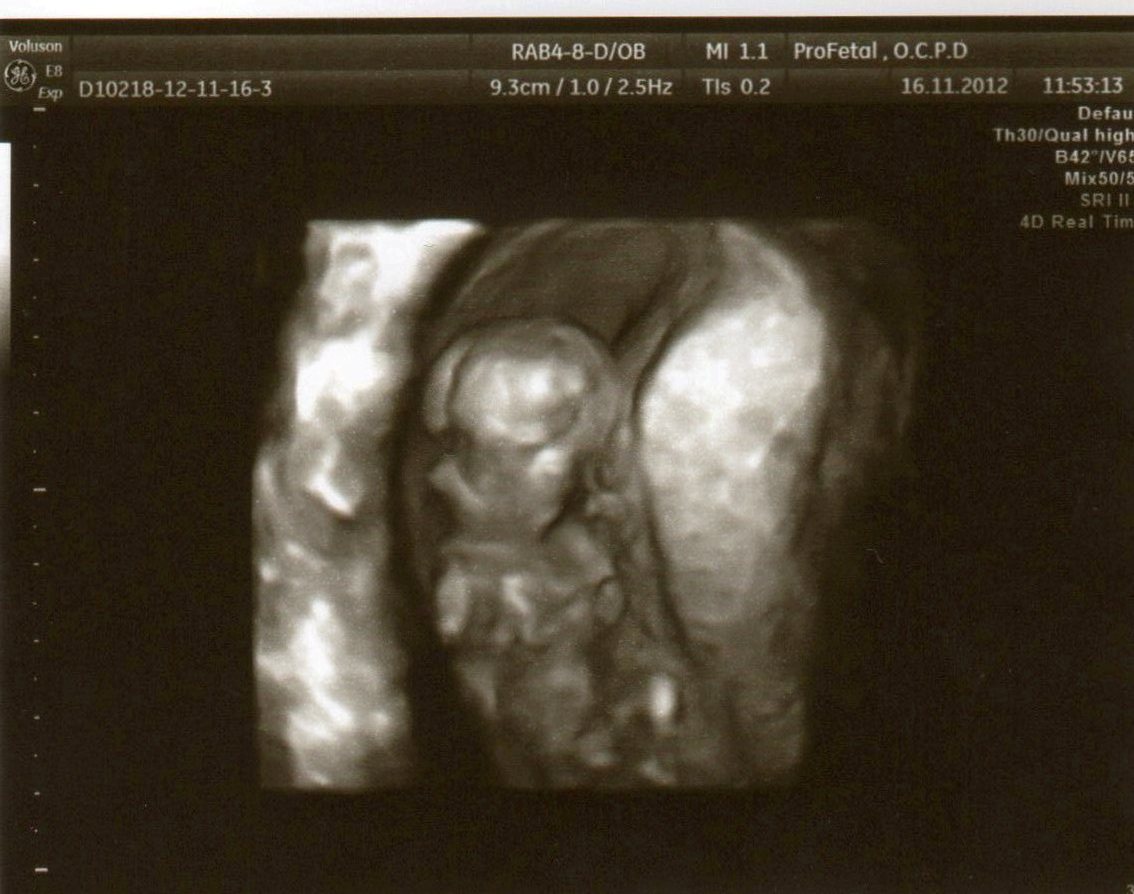

@maximsarah já jsem bohužel na tohle docela nemožná a většinou nikde nevidím nic ☹ ale jestli to nevadí, ráda bych se tady také zeptala, máme ale fotky teprve ze 13. týdne, doktor nám svůj tip řekl, podle té první bych řekla, že to tam vidět je, ale v tomto týdnu je to prý u obou pohlaví trochu podobné tak nevím........spíš by mě zajímalo jestli někdo nemá také podobné fotky z tohoto týdne a přidá názor 🙂

@michaela_2 v tomhle tt se pohlavi vetsinou urcuje podle vnitrnich organu... To fakt musi lekar pri utz

@mamkamarketa jj. on nám to říkal podle močové trubice - že je prý nějak jakože zatočená, takže to bývají kluci, když je rovná tak to bývá holčička 🙂 Já jen zkoušela jestli někdo nemá třeba také fotku z tohoto týdne pro porovnání

@michaela_2 Fotečku z boku máme taky ale tam už bohužel nevidím vůbec nic 🙂 Budeme se muset nechat překvapit...

@michaela_2 já si teda myslím chlapečka🙂 Ale je to jen hrubý odhad😀 Nám řekl svůj typ doktor ve 20tt, potom mi to potvrdila až v porodnici doktorka🙂